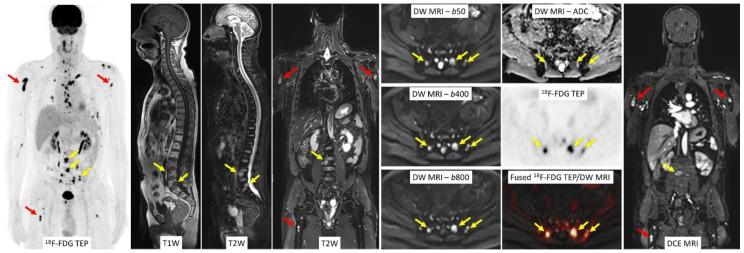

Bone disease is one of the major features of multiple myeloma (MM), and imaging has a pivotal role in both diagnosis and follow-up. Whole-body magnetic resonance imaging (MRI) is recognized as the gold standard for the detection of bone marrow involvement, owing to its high sensitivity. The use of functional MRI sequences further improved the performances of whole-body MRI in the setting of MM. Whole-body diffusion-weighted (DW) MRI is the most attractive functional technique and its systematic implementation in general clinical practice is now recommended by the International Myeloma Working Group. Whole-body dynamic contrast-enhanced (DCE) MRI might provide further information on lesions vascularity and help evaluate response to treatment. Whole Body PET/MRI is an emerging hybrid imaging technique that offers the opportunity to combine information on morphology, fat content of bone marrow, bone marrow cellularity and vascularization, and metabolic activity. Whole-body PET/MRI allows a one-stop-shop examination, including the most sensitive technique for detecting bone marrow involvement, and the most recognized technique for treatment response evaluation. This review aims at providing an overview on the value of whole-body MRI, including DW and DCE MRI, and combined whole-body F-FDG PET/MRI in diagnosis, staging, and response evaluation in patients with MM.